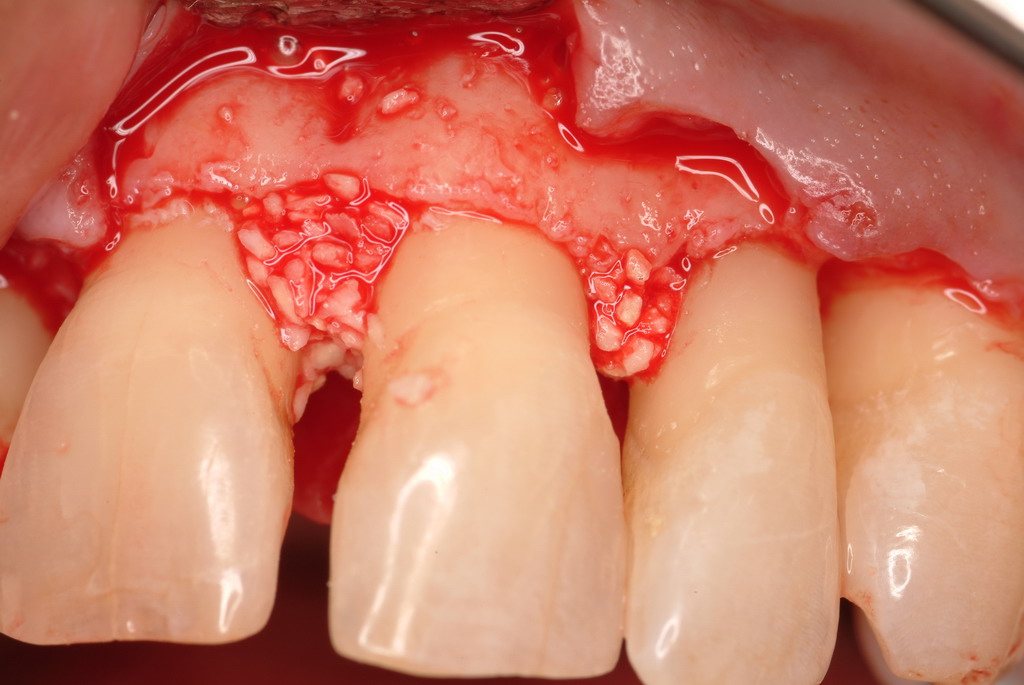

The patient had been referred for an implant consultation for the mandibular right canine. She had very deep probing depths on the lingual. When the flap was raised, a significant amount of subgingival calculus was seen as a local risk factor (Figure 18). However, she had no significant pathology to remove from the situation. Debridement was performed the same as in Case 3 with the rotary ultrasonic and manual instrumentation.

The defect was obturated with mineralized freeze-dried bone and hydrated with platelet-derived growth factor. As with any growth factor, when implementing it clinically, all growth factors require a carrier to bring that growth factor to the desired site, which do not elicit an inflammatory response. In this situation, it is the mineralized freeze-dried bone allograft. This combination was demonstrated by Rosen et al8 to be efficacious in treating intrabony defects. A biologic approach was taken both in terms of the graft and membrane (Figure 19). Primary closure was achieved.

Subgingival calculus and severe bone loss.

Figure 18